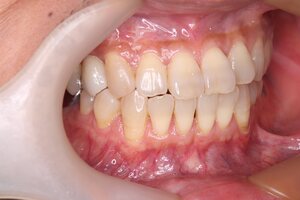

治療中①

治療中②

年齢・性別 30代・女性

主訴 左下6番、左下7番のインプラント

治療内容 左下5〜7番のブリッジだったが、支台の左下7番が破折のため抜歯となった。その為左下6番、左下7番にインプラントを2本埋入した。

抜歯時間 10ヶ月

抜歯費用 合計:1,045,000円